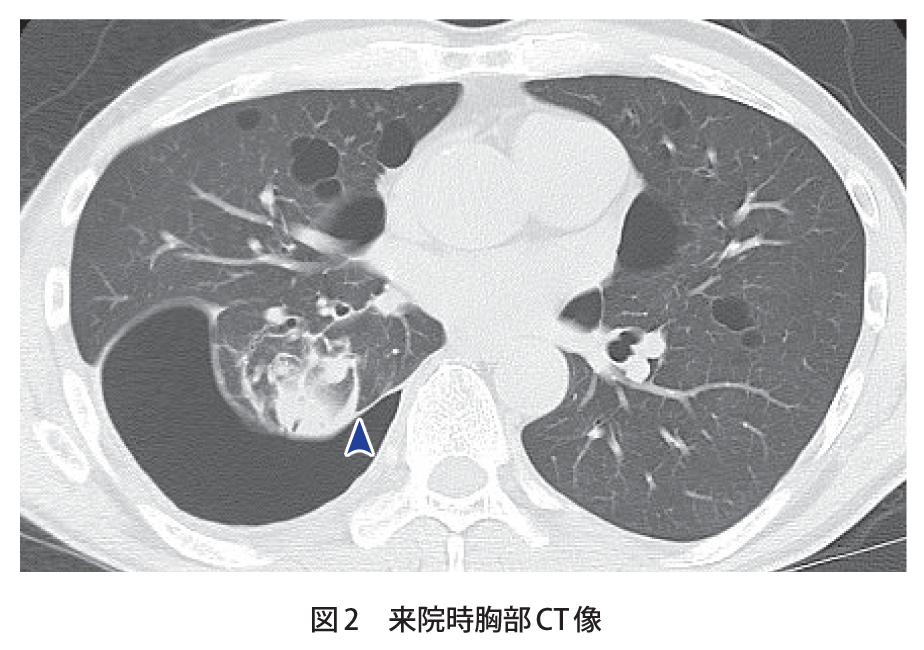

円形無気肺の画像所見 円形あるいは類円形の腫瘤影 を形成する。 胸膜肥厚 を伴うことが多い。 胸水 の既往があることが多い。 無気肺部に向かって近くの気管支と動脈が、弯曲する comettail sign(彗星の尾に似ている) を認めることあり。 症例 80歳代男性キー画像54 気管支内に鋳型状に充満する腫瘍と末梢肺の変化 末梢側:粘液栓、エアートラッピング、無気肺 ※白黒反転画像では、fingeringlove sign、treeinbud signの検出が容易で、またエアートラッピングのコントラストも良好。左下葉無気肺が生じている(左下肺野心 陰影に重なる部分の透過性低下,下行大動脈左側縁および左横隔 膜影は不明瞭化し,左肺全体の容積減少)。 c.左下葉支基部の扁平上皮癌により左下葉は完全無気肺に陥って いるのがct画像により確認できる。